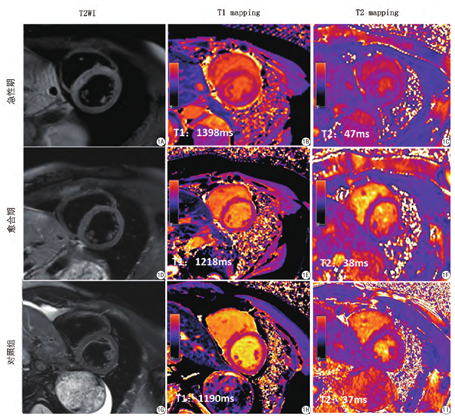

与愈合期相比,急性期患者整体原始T1[1414 (1357,1459) vs 1267(1249,1298),P<0.001]、T2[47(43,49) vs 39(38,43),P<0.001]、ECV [0.36(0.32,0.40) vs 0.29 (0.26,0.30),P<0.001]值明显升高。愈合期患者原始T1、T2及ECV值明显高于正常对照组。典型病例见图1。